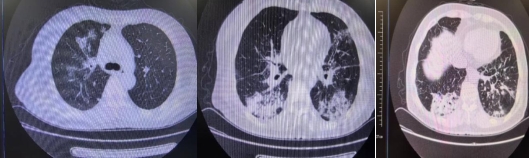

患者入院時胸部CT